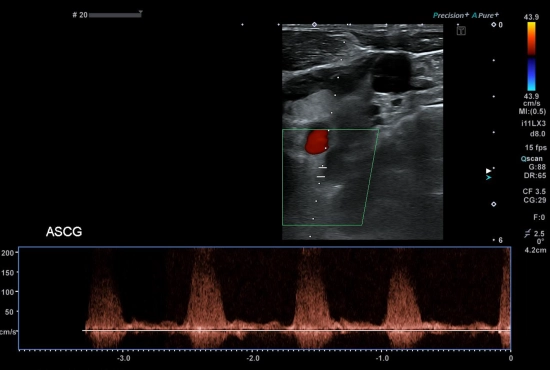

"Quand une douleur testiculaire cache une hernie inguinale : l'importance de l'exploration systématique des orifices herniaires"

25/04/2026

Lire la suite